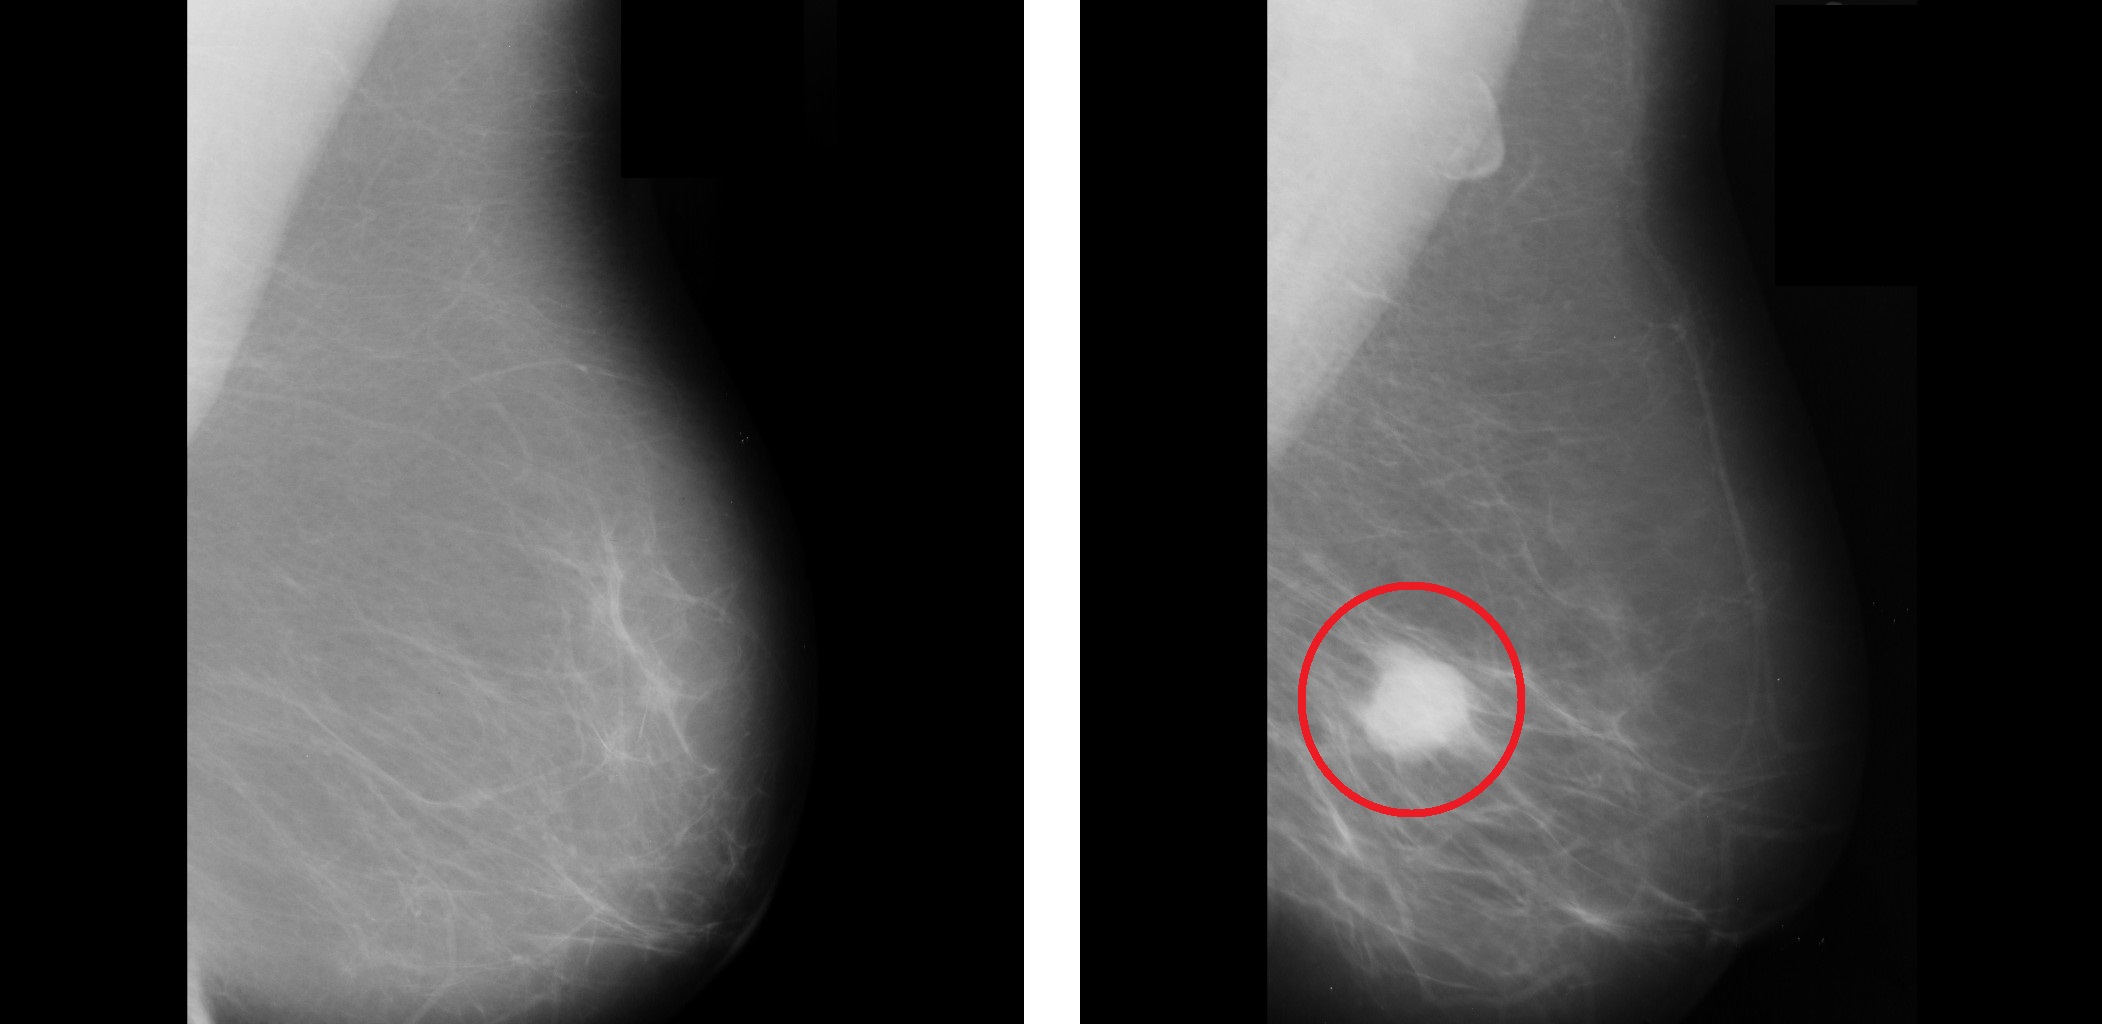

This research addresses the development of multimedia mining projects by applying analytical techniques to texts, images, audio, and video. In order to develop these projects, a methodology to develop multimedia mining projects (Multimedia Analytical Methodology-MAM) is proposed. Likewise, the construction of a software tool (known as Multimedia Analytical Platform-PAM) which allows the analysis of multimedia mining is introduced. Methodology and platform are evaluated with two study cases on prediction of mammography abnormalities and analysis of medical imaging similarity. Results obtained allowed validating the steps proposed in the MAM methodology and using the PAM platform to extract the characteristics of medical images, to apply data mining techniques, and to satisfactorily evaluate the results obtained.